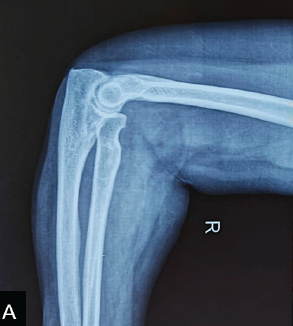

Femoral Neck Fractures, the Unsolved Enigma: Where Error is Costly, and Preservation is Priceless

Jayaramaraju Dheenadhayalan , Janki Sharan Bhadani , Ashok Shyam , John Mukhopadhaya

………………………………p.1-3